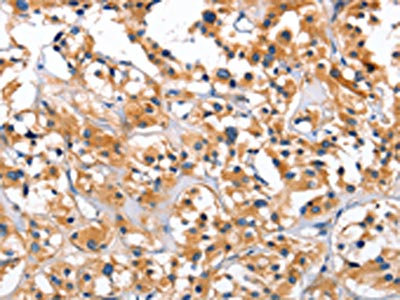

• The image on the left is immunohistochemistry of paraffin-embedded Human tonsil tissue using CSB-PA966396(CEP97 Antibody) at dilution 1/40, on the right is treated with fusion protein. (Original magnification: ×200)

• The image on the left is immunohistochemistry of paraffin-embedded Human thyroid cancer tissue using CSB-PA966396(CEP97 Antibody) at dilution 1/40, on the right is treated with fusion protein. (Original magnification: ×200)